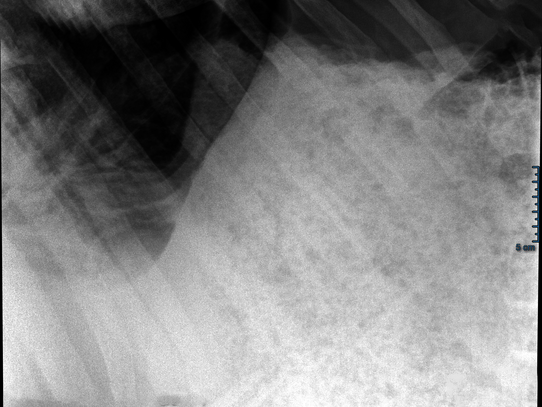

Case 3: Common wombat

Wombat Windemere (born in 2020) suffered from diarrhea, loss of appetite, and balance problems in the fall of 2024. After unremarkable laboratory findings, a comprehensive examination was performed under inhalation anesthesia, including an X-ray of the abdomen. The findings showed a high accumulation of gas in the gastrointestinal tract. The diagnosis: dysbiosis (imbalance in the intestinal flora). A change in diet from sweet potatoes to fiber-rich bamboo, as well as vitamin supplements, brought about a rapid improvement—Windemere was back to health a few days later and was allowed to return to his partner Wendy in the enclosure.